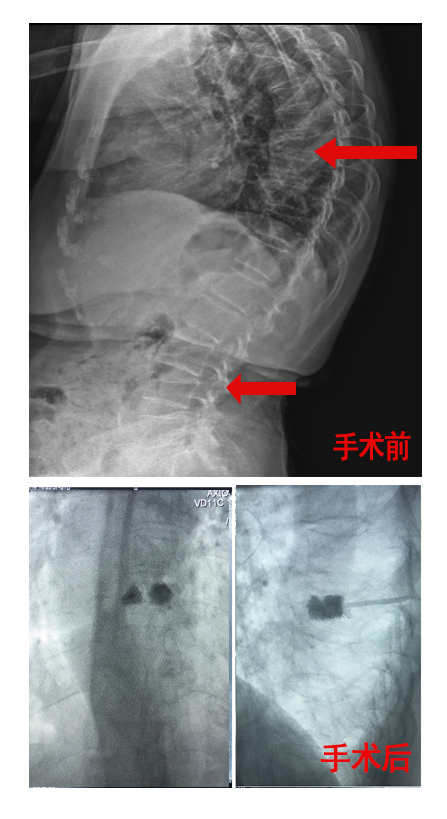

患者王某某,女,78岁,主因“间断腰部疼痛3年,背部疼痛1周”入院。入院后行胸腰椎片、胸腰椎MRI显示“胸8椎体压缩性骨折(新发),腰4椎体压缩性骨折(陈旧性)”。给予规范的内科抗骨质疏松药物治疗,并在介入室局麻下行胸8椎经皮球囊椎体后凸成形术(PKP),术后患者疼痛明显缓解。

↓ 患者王某手术前后对比图: